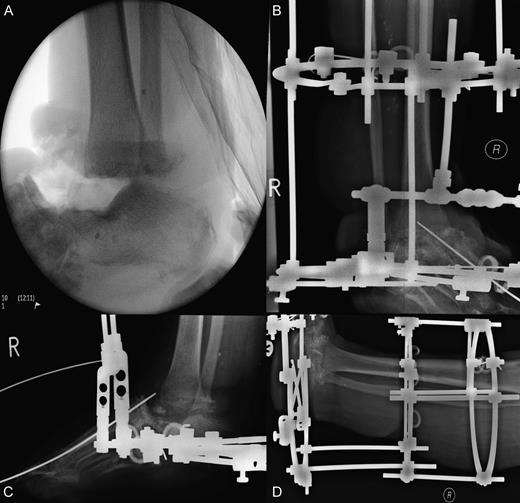

Wound debridement demonstrated pus at screw insertion sites with navicular and talar involvement. The patient had inadequate soft tissue coverage, bony osteomyelitis and necrotic bone. Primary limb shortening with a talectomy was conducted to reduce the soft tissue deficit and remove infected and necrotic bone, tibiocalcaneal arthrodesis for joint stability using external fixation, and dead space was treated with calcium sulphate mixed with vancomycin and systemic intravenous and oral antibiotics for osteomyelitis postoperatively (Figs 3 and 4). The wound was closed after the external fixator was applied. Wound swabs and bone samples revealed Enterococcus faecalis and E. raffinosus and diphtheroids. The patient was treated with intravenous teicoplanin and meropenem with oral stepdown to linezolid and ciprofloxacin.

Surgical images of talectomy and external fixation used for tibiocalcaneal arthrodesis. (A) Anterior posterior intraoperative radiograph illustrating talectomy. (B–D) Radiographs showing external fixation in situ.